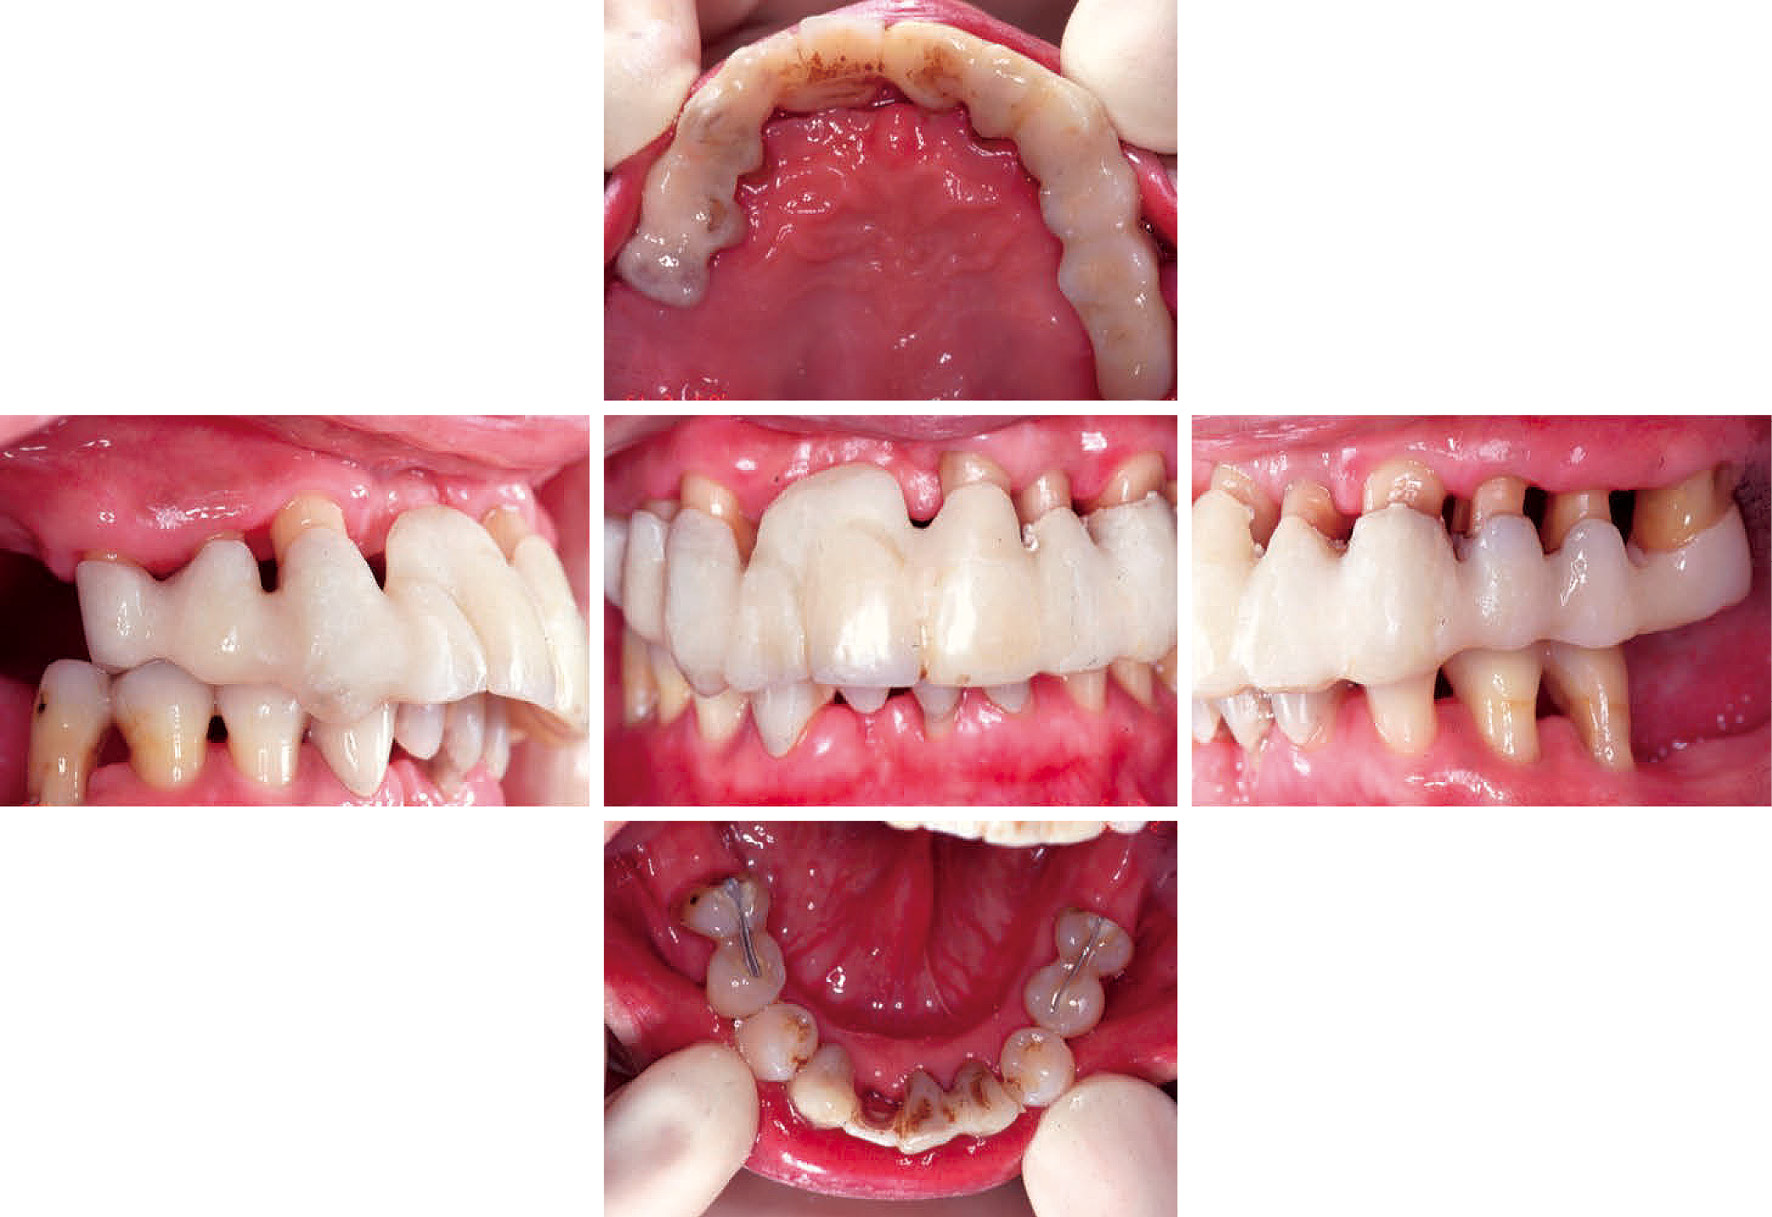

初診より2年5ヶ月経過した再評価において,全顎PDは3 mm以下,BOP(-)を全ポケットで達成し,PCR値も10~15%で安定しているため,治癒良好と判断し,SPTに移行した。この時の病態写真(図5)より,補綴物を装着後,プラークコントロールはいっそう良好となり,歯肉の健康も獲得できた。

SPT開始時の口腔内写真(初診より2年5ヶ月後)